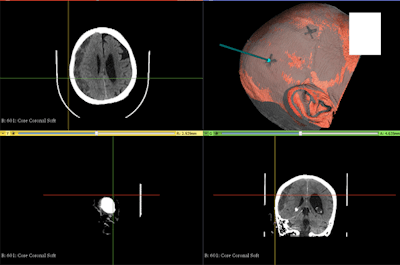

The researchers tested their 3D scanning technique on a 3D-printed head model, which they generated using CT data. The 3D scanning technique involved projecting light patterns from a multimedia projector onto the 3D-printed head and capturing the patterns with a camera. An algorithm then used these light patterns to generate a virtual 3D model of the head.

Finally, the researchers registered the virtual 3D model to CT scans of the 3D-printed model to determine the ideal entry point for SEPS placement. They tested their technique 10 times and calculated an average registration error of less than 2 mm, confirming the accuracy of the method.

Following the success of these early tests, the researchers applied their 3D navigation technique to five SEPS placement procedures for patients requiring chronic subdural hematoma evacuation. Obtaining an accurate 3D light scan of a patient's head using the technique took an average of 1 to 2 minutes.

Overall, Bow and colleagues found that the new 3D navigation technique was highly accurate at suggesting the optimal site for SEPS placement. The average distance between the anticipated SEPS burr hole location (based on registration of the virtual 3D model to CT scans) and the actual burr hole location was less than 1 cm, which falls within the acceptable error limit for SEPS placement.